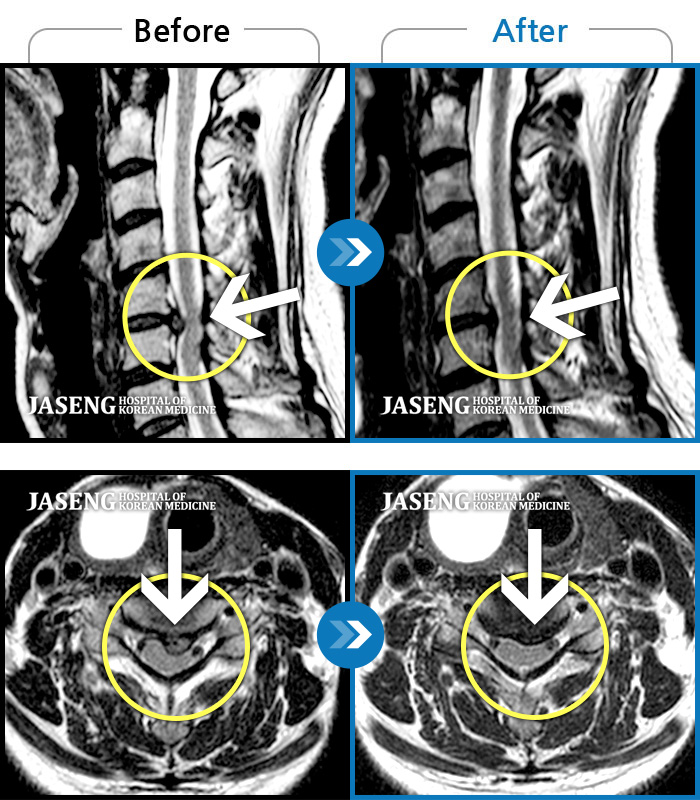

Before

After

허리 통증과 함께 발끝 저림이 1년 이상 되었으며 최근 1-2개월 사이에 증상이 급격히 심해져 우측 다리 앞 뒤가 당기고 힘이 빠져 본원에 내원함

2023.11.20 ~ 2024.08.12